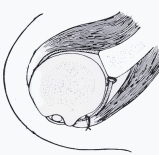

Los mecanismos pasivos están dados por la conformación articular, volumen articular, mecanismo de presión negativa, estructuras capsulares y ligamentarias, labrum glenoideo y estructuras óseas. En toda la literatura ortopédica hay discusión sobre cuál sería la lesión esencial que determinaría la recurrencia después de una lesión traumática, la presencia de una lesión, desinserción del labrum, la laxitud capsulo-ligamentaria congénita o traumática o la lesión ósea postero-lateral de la cabeza humeral (lesión de Hill-Sach) son implicadas en la génesis de la LRH (6). En las últimas décadas se ha dado mayor importancia a la lesión del complejo labrum-capsular , el labrum de la glenoide es un anillo fibroso que sirve para dar profundidad a la cavidad glenoidea y permite la fijación de los ligamentos gleno-humerales, el tendón del bíceps en la parte superior (4). Bankart en 1923 consideraba la desinserción de la glenoides como la lesión esencial responsable por la alta incidencia de LHR.